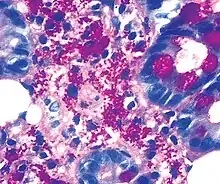

Coloration PAS

La coloration PAS (Periodic Acid Schiff) est une coloration utilisée en histologie pour mettre en évidence les polysaccharides (types mucopolysaccharides) présents dans certains tissus conjonctifs ainsi que dans le mucus. Elle est composée d'acide periodique et de réactif de Schiff.

Il colore en rouge fuchsia les aldéhydes (sucres ou polysaccharides) de la membrane plasmique ou des acides nucléiques. Le glycogène et les glycoprotéines apparaissent roses. Ces groupements glycols apparaissent dans la membrane basale (située par exemple à l'interface entre l'épithélium et le tissu conjonctif).